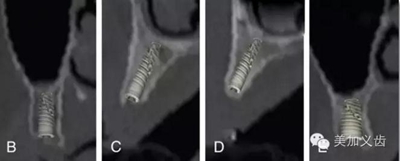

其優(yōu)點是:可以提供精確的、亞毫米級測量數(shù)值,與印模結(jié)合,通過CBCT數(shù)據(jù)來實現(xiàn)模擬手術(shù)并制作外科導(dǎo)板。CBCT的放射量與傳統(tǒng)CT相比要小很多,放射時間短,操作也比較簡單。

現(xiàn)在很多廠家都能夠制作外科導(dǎo)板了,醫(yī)生把CBCT數(shù)據(jù)和石膏模型發(fā)送給加工廠,加工廠通過軟件設(shè)計來進行虛擬種植,就能通過3D打印技術(shù)或者CAD/CAM做出手術(shù)導(dǎo)板。你不用管他們是怎么做的,總之你能得到一個手術(shù)導(dǎo)板,有了導(dǎo)板的幫助,種植手術(shù)的難度會降低很多,尤其是多顆牙的種植手術(shù)。

9.jpg

其缺點是:設(shè)備成本還是比較高,分辨率略顯不足,而且會存在一定程度上的影像學(xué)偽影。